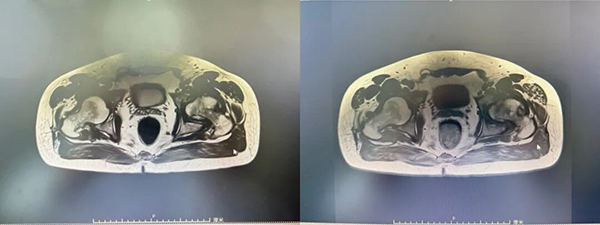

术前MRI: